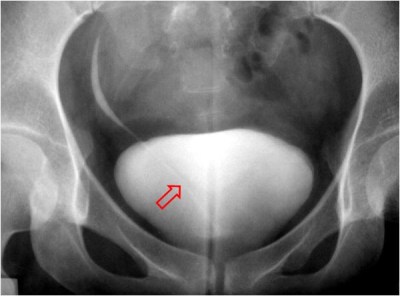

Signo que permite diferenciar un falso defecto de repleción vesical en la urografía debido a gas superpuesto, de un verdadero defecto por lesión intravesical. Consiste en la presencia de una delgada línea blanca, de unos 2 mm, que rodea al falso defecto y que corresponde a la pared rectal delimitada por el gas y por la grasa de los tejidos blandos circundantes.

El valor de este signo es muy relativo, ya que, cuando la repleción vesical no es completa, puede verse una imagen similar alrededor de un tumor vesical. Además, la presencia del gas en la radiografía de abdomen previa, el cambio de su morfología a lo largo del estudio o la falta de superposición en proyecciones oblicuas son más útiles. En la imagen vemos el gas rectal en la placa simple realizada antes de la administración de contraste. Las flechas marcan la línea blanca de la pared rectal.